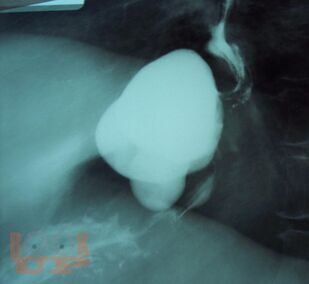

Рентгенодиагностика дивертикулов пищевода, желудка и двенадцатиперстной кишки

В методическом пособии на основании многолетнего личного опыта автора и литературных данных изложены основные сведения о диагностике дивертикулов пищевода, желудка и двенадцатиперстной кишки.